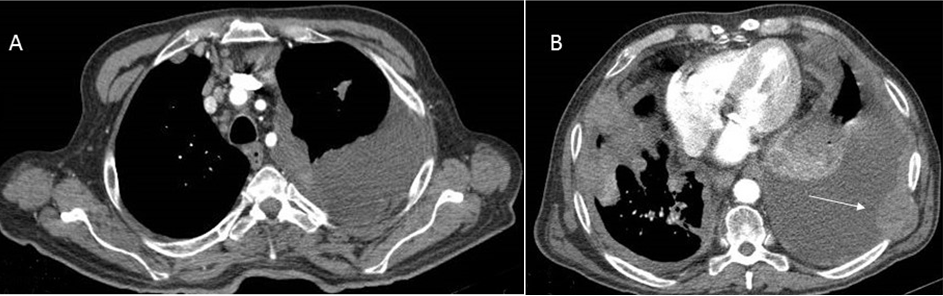

We report a case of a 64-year-old non-smoking male, who had had intermittent exposure to asbestos for three years. He had been undergoing treatment for hypertension. He presented with dyspnea on moderate exertion that had developed over several days, discomfort in the left hemithorax, and some intolerance to decubitus positions. The patient had a weight loss 10 kg in the last three months. A physical examination showed that he was conscious and lucid with normal coloring. Respiratory auscultation revealed hypophonesis in the lower half of the left hemithorax and right basal hemithorax. Hematological and hepatic findings were within the normal range. Tumor markers carbohydrate antigen (CA) 125, carcinoembryonic antigen (CEA), alpha-fetoprotein (AFP), CA 15-3, and CA 19-9 were shown to be within the normal range. Simple radiography of the posterior-anterior thorax showed bilateral pleural effusion with multiple nodular images in both hemithoraces (Figure 1). A contrast computed tomography (CT) scan of the thorax and abdomen revealed multiple bilateral pulmonary and pleural lesions, mediastinal lymphadenopathies (Figure 2), intra-abdominal implants (Figure 3), and a 56×40 mm polylobulated mass in the left buttock (Figure 4). A biopsy of the mass in the left buttock was made with an 18-gauge needle. Pathological study involved obtaining three cores of tissue measuring between 0.7 and 1 cm in length that were fixed in formalin. In the histological sections, we observed connective tissue infiltrated by epithelioid cells arranged in nests and trabeculae that showed atypia with hyperchromatic nuclei and prominent nucleoli. Occasional non-atypical mitosis was also detected (Figure 5). Immunohistochemical study revealed cytoplasmic positivity for keratins 5/6 and 7. Nuclear and cytoplasmic positivity was observed for calretinin, while nuclear positivity was detected for Wilms tumor 1 protein (Figure 6). Negative results were found for epithelial membrane antigen (Ber-Ep4), thyroid transcription factor-1 (TTF-1), protein suppressor p63, keratin 20, CEA, prostate-specific antigen (PSA), renal cell carcinoma (RCC), vimentin, common lymphoblastic leukemia antigen (CD10), S-100 protein, and CA 19.9. These results confirmed the diagnosis of metastasis of epithelioid mesothelioma. The patient passed away eight days later.

Figure 2: Contrast computed tomography scan of the thorax. (A) Pleural-based mass with heterogeneous enhancement throughout the left mediastinal surface together with multiple lymphadenopathies in the prevascular and right paratracheal spaces, and (B) Pleural effusion and bilateral metastasis predominantly on the left with involvement of the left thoracic wall.